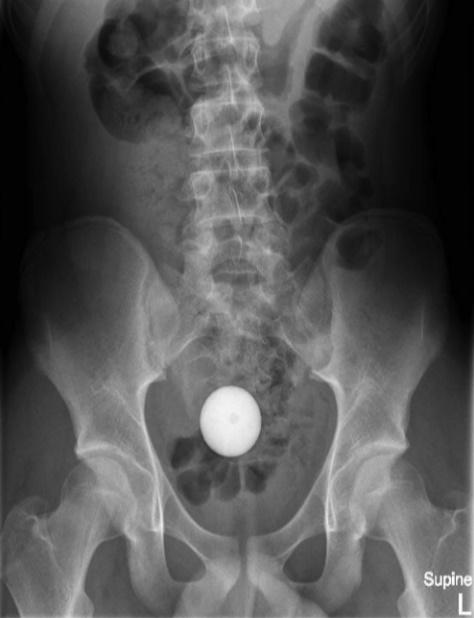

報告指出,這名少年將高爾夫球塞進自己的肛門,惟愈塞愈深,最後竟塞進腸道,雖然少年指無感到劇烈疼痛,但眼見自己已無法處理,只好向母親求助前往就醫。少年指出,雖然球球跑進體內,但他並沒有感受到劇烈疼痛感。X光顯示,一顆球體就在腹腔內。醫生決定先後使用醫療網、導管、吸引器等6種方法,希望將高爾夫球取出但失敗,折騰了2小時後,醫生亦要暫停休息。